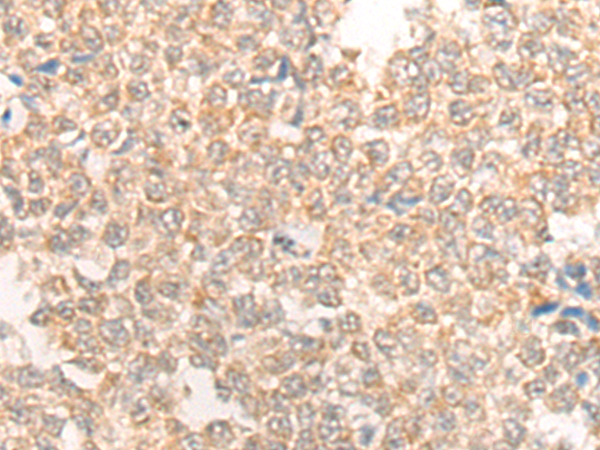

分类: 科研抗体货号: P00649别名: BFLS; BORJ; CENP-31应用: IHC反应种属: Human, Mouse